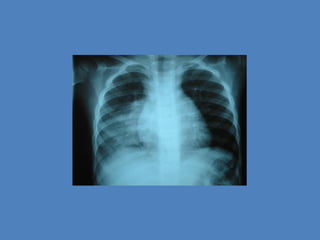

NEUMONIA 1

• ANTE LAS IMÁGENES DE CONDENSACION DE

LOBULO SUPERIOR IMÁGENES DIFUSA Y

ATELECTASIAS LAMINARES SE DIAGNOSTICA

• UNA NUEVA RX CON IMÁGENES DE LOBULOS

SUPERIORES CON INFILTRADOS

INTERSTICIALES DIFUSOS DE TIPO PERIFERICO

• CARACTERISTICAS RADIOLOGICAS TIPICAS DE INFILTRADOS DIFUSOS

EXTENSOS BILATERALES A PREDOMINIO DE LOB SUPERIORES

“IMAGEN NEGATIVA DE EDEMA DE PULMON”